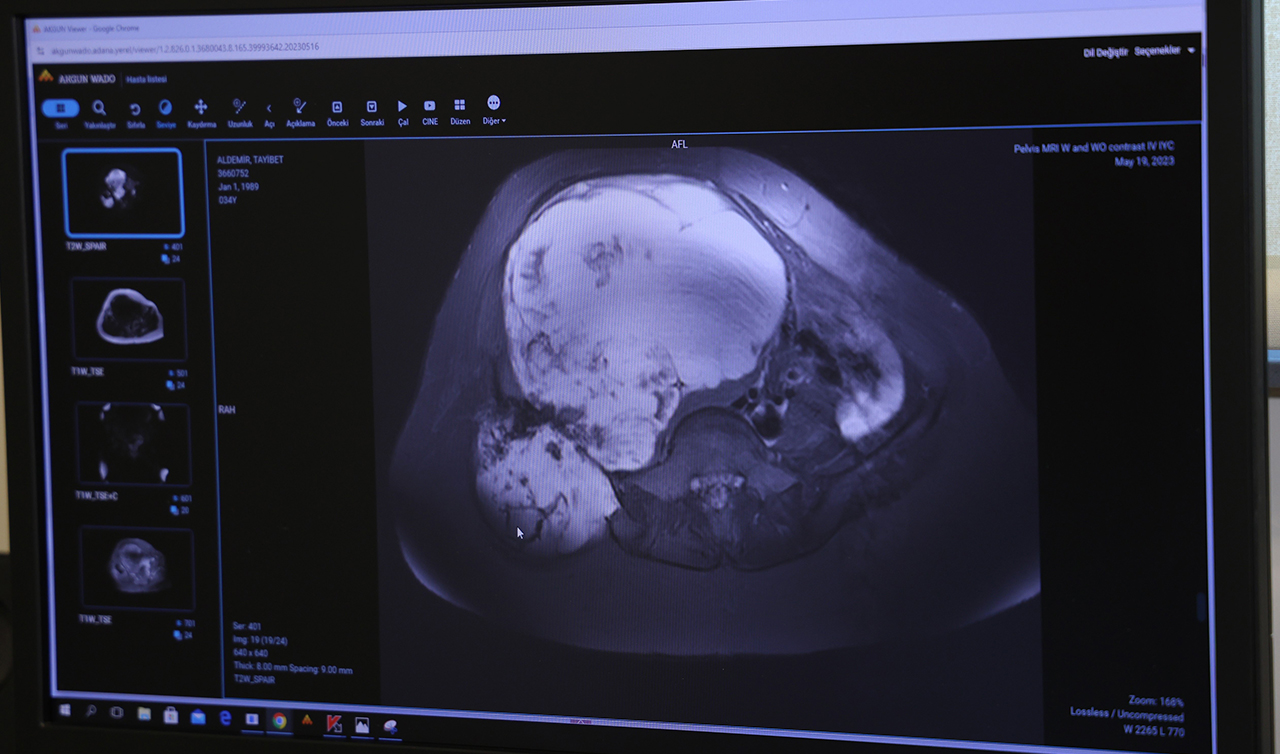

Burada Ortopedi ve Travmatoloji Kliniği'nde görevli Prof. Dr. Ahmet Kapukaya'ya başvuran Aldemir, yapılan tetkikler sonucu doktorunun da yönlendirmesiyle ameliyat olmaya karar verdi. Türkiye'de nadir yapılan ve 6 saat süren ‘Pelvik rezeksiyon' ameliyatıyla genç kadının leğen kemiğindeki tümör temizlendi.

İhlas Haber Ajansı'na konuşan Ortopedi ve Travmatoloji Uzmanı Prof. Dr. Ahmet Kapukaya, “Hastamız bize geldiğinde tümörü çok ilerlemişti. Ameliyat olması halinde yüzde 98 bacak kaybı, yüzde 95'de ölüm riski var denilmişti. Ancak Adana Şehir Eğitim ve Araştırma Hastanemizin alt yapısı bu tür ameliyatları yapmaya çok müsait. Bizde hastamıza riskleri anlattık ve ekip halinde bu ameliyatı gerçekleştirdik. Leğen kemiğini bölgeden çıkarttık, tümörü temizledik ve vücuttan alınan diğer kemiklerle o bölgede yeni bir leğen kemiği oluşması için kaynamaya bıraktık” diye konuştu.